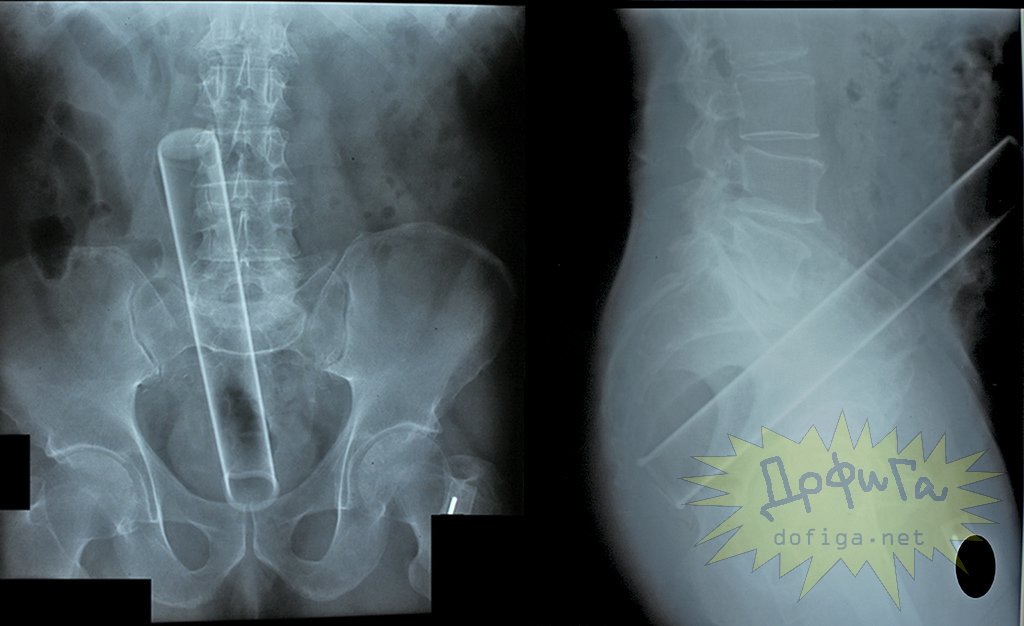

アナルに ”何かしら” を突っ込んで取れなくなってしまう人たちは意外に多いみたいで、そんな人たちのレントゲン写真を集めたギャラリー[13]images